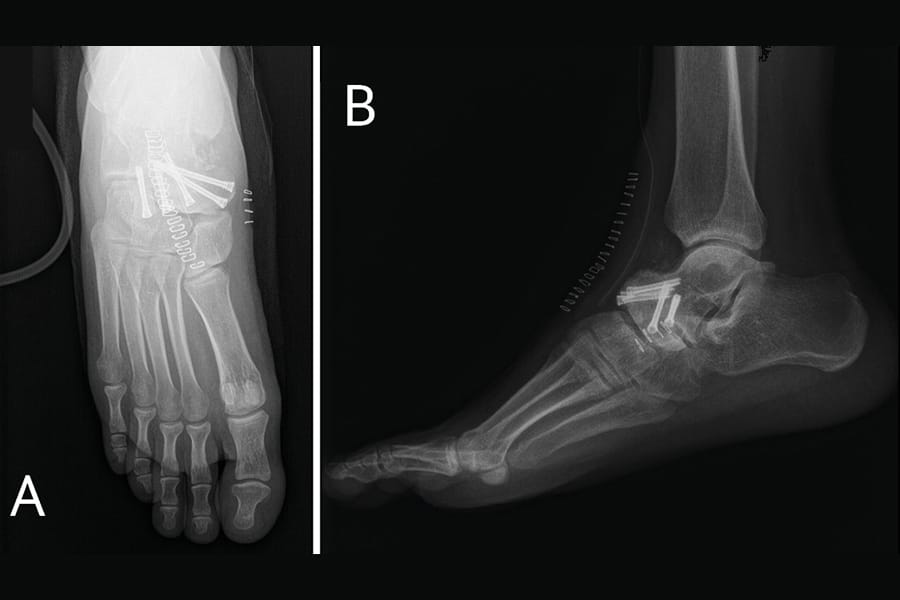

Coin de l'interne Arthrodèse isolée de la talo-naviculaire indications, technique chirurgicale et pièges , Marion Di Schino Cabinet SPORTHO 30, Nîmes, France N°350 - Janvier 2026 ● 10 min de lecture